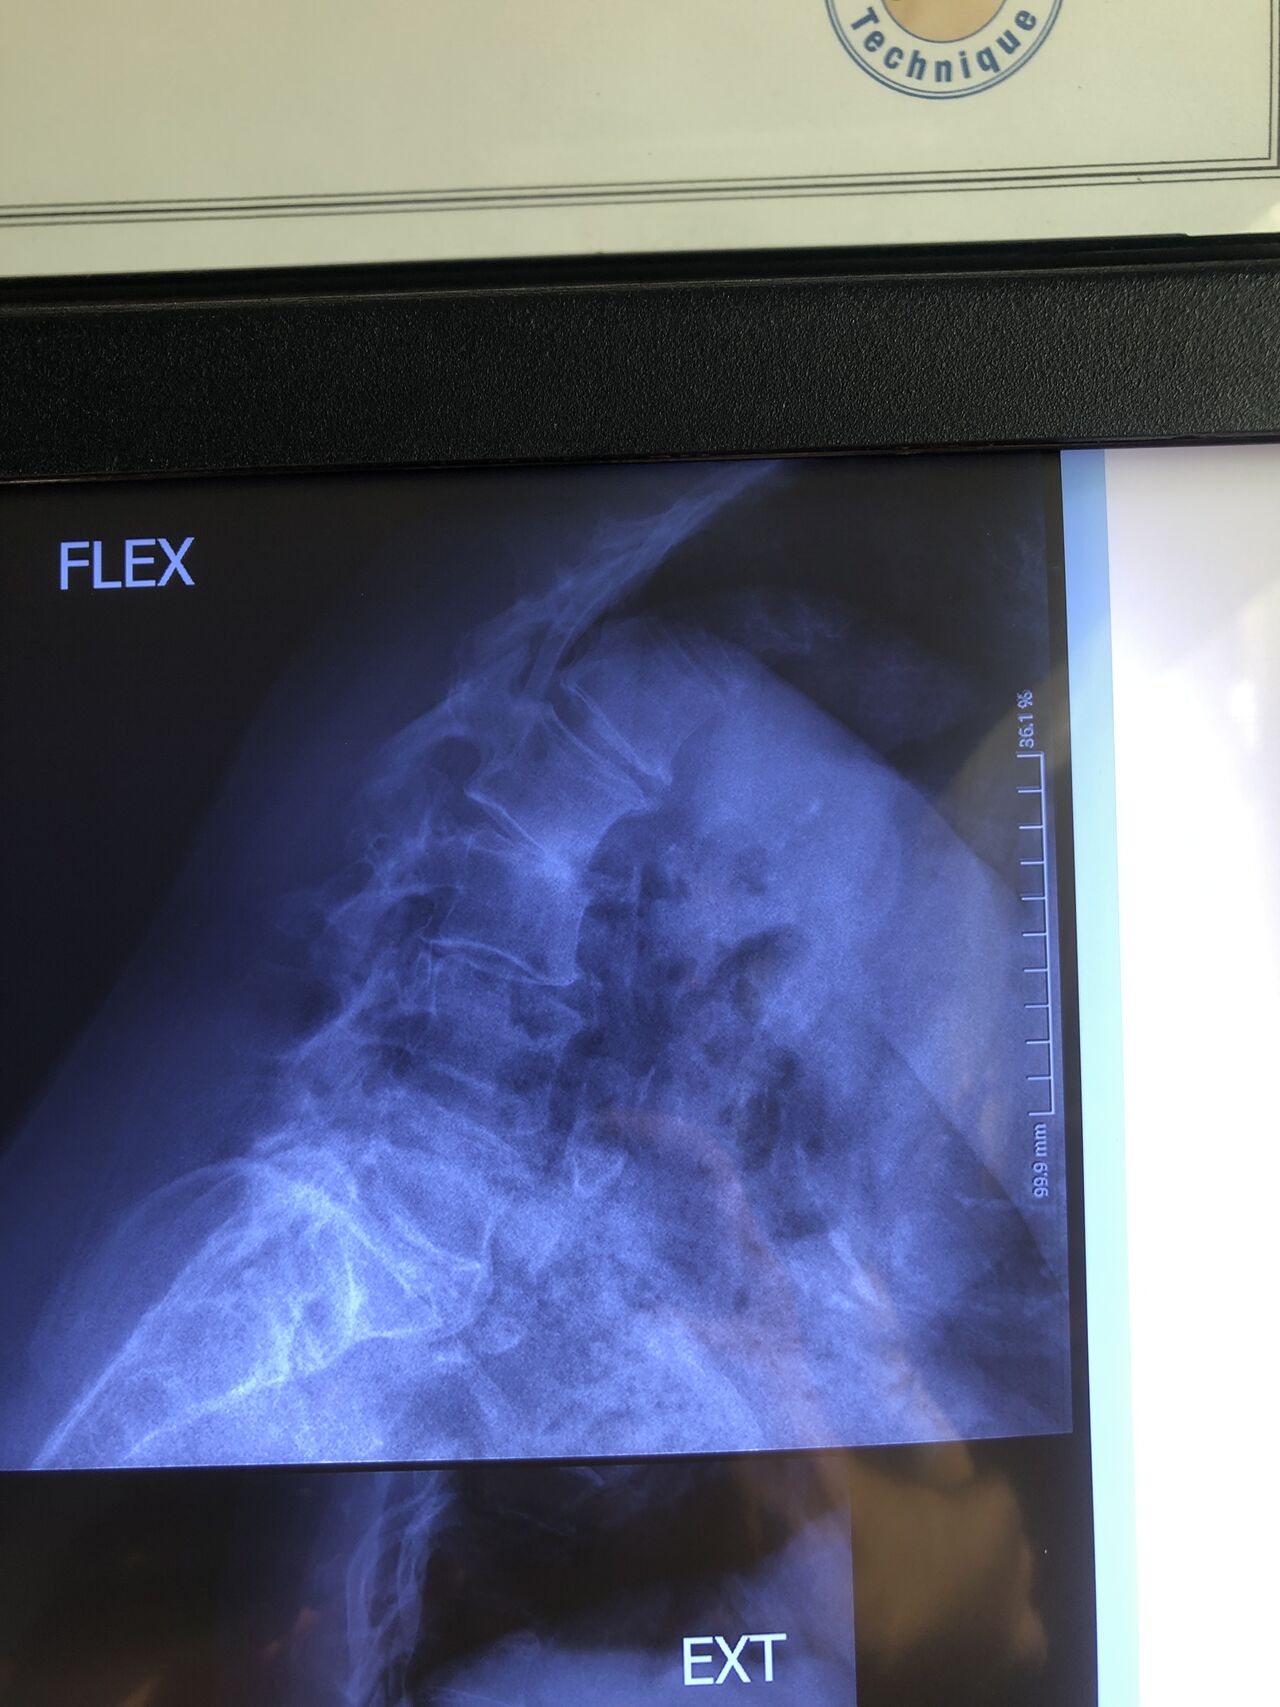

This time presented to my cl with LBP mainly during sleep at night. Just brought me her mri. According to her mri I ordered dynamic L/S X. R.

I didn’t accept her to give treatment. I referred her to her surgeon. What are your findings in her mri and X. Rays?

Is ant listhesis of L4 unstable or stable?

From several compression fractures we see which of is acute/ subacute and which ones are chronic fx?